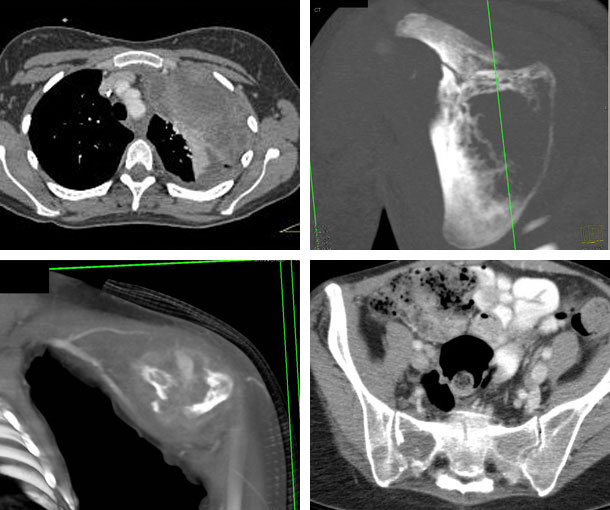

Ewing Sarcoma CT Findings

- Destruction of the bone (“moth eaten” pattern)

- Lytic lesions with poor margination

- Most common in the pelvis, long bones, and ribs

- Isodense

- Usually does not calcify

- Medullary canal is usually involved

- Periosteal new bone formation

- Soft tissue mass that usually does not calcify